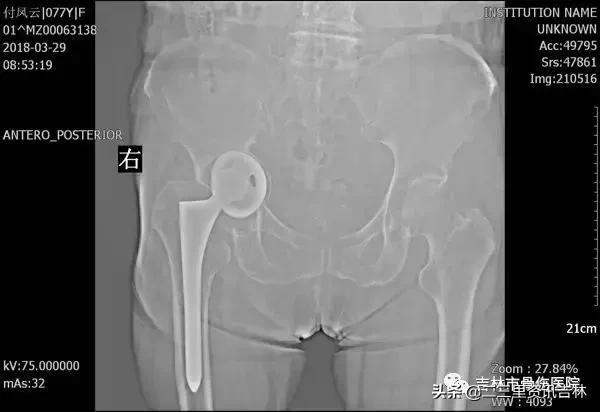

该患于2010年因右股骨颈骨折在外院行右侧人工全髋关节置换术,术后恢复良好,休养至今,于1年前右髋部出现隐痛,休息后未见缓解,逐渐加重,近一个月加重明显,现行走跛行,为求系统治疗前来我院就诊,经门诊医生查体、拍片后以“右侧人工全髋关节置换术后疼痛”收入院。

2018年3月拍片

X线片示:右侧人工髋关节置换术后影像,髋臼内陷,髋臼壁薄弱,原有的髋臼结构及承重结构已破坏、消失,股骨柄下沉,余未见明显异常。

患者入院后给予常规检查,经三级医师查房,临床诊断确诊,经过科内及院内医生会诊,查无明显手术禁忌症后在腰硬+全麻下行“右侧全髋关节置换术后假体松动关节翻修术”,术中我们沿原手术切口瘢痕切开皮肤、皮下及深筋膜,切开关节囊,活动髋臼杯见髋臼杯假体活动,依次取出内衬及髋臼杯,见髋臼内陷,髋臼壁薄弱,原有的髋臼结构及承重结构已破坏、消失,我们取同种异体骨材料用咬骨钳处理成大小不一的若干个骨块,万古霉均匀素涂后倒入髋臼处,*压打**植骨,抹平后用髋臼锉处理髋臼,脉冲冲洗,外用万古霉素,然后根据术前测量的髋臼大小,置入型号为Φ64/32mm3D打印金属髋臼,活动髋臼较稳定,并以3枚螺钉固定,放入内衬,活动内衬较稳定。活动原有股骨柄假体见略有微动,用打拔器取出原有股骨柄,髓腔挫扩髓,植入型号为8#的股骨柄,安装32mm球头。复位,试行关节外展、内收、前屈、后伸、旋转各方向活动,见关节稳定性良好,纵向牵拉,活动度约1厘米。对比健侧,双下肢基本等长。逐层缝合,术终。术后给予抗感染、消肿、抗凝关节功能松动练习等对症治疗,术后患者自诉疼痛明显减轻,现患者及其家属对当前治疗表示满意。